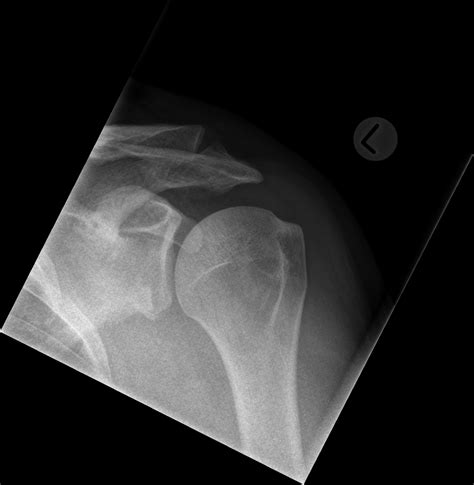

• Imaging studies: Imaging studies, such as X-rays, CT scans, or MRI scans, can help visualize the Hill Sachs lesion and assess its size and location. MRI scans are particularly useful for evaluating the soft tissues around the shoulder joint.

• hill sachs defect xray